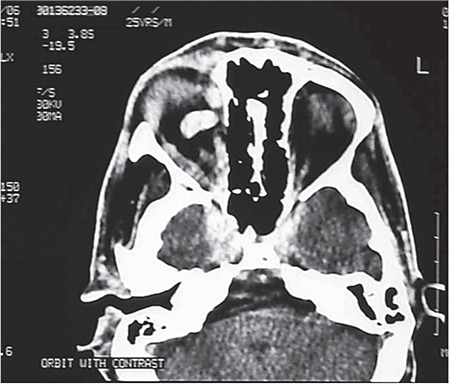

Materials and methods: This retrospective interventional case series included 18 patients who underwent endovascular balloon embolization from 2019 to 2022 at Lahore General Hospital in Lahore, Pakistan. The analyzed data consisted of age, gender, cause and type of CCF, clinical presentation, diagnostic technique used, intervention, and the results of two-month follow-up. Patients with incomplete records and coil embolization were excluded. Digital subtraction angiography was done in all cases followed by endo-arterial balloon embolization. Procedures were carried out under general anesthesia via femoral artery approach. A single balloon was sufficient to close the fistula in all cases.

Results: There were 18 patients who met the inclusion criteria. Sixteen patients had direct CCF, and the mean age of the patients was 27.2±12.6 years. The commonest cause of CCF was trauma, and the mean time of presentation after trauma was 7.89±7.19 months. The male-to-female ratio was 8:1. Preoperative visual acuity was worse than 6/60 in 8 patients, between 6/60 and 6/18 in 7 patients, and better than 6/18 in 3 patients. The mean intraocular pressure was 16.06±3.37 mmHg preoperatively and 14.83±3.49 mmHg postoperatively (p=0.005). Endovascular embolization was successful in 15 patients (83.3%). One patient developed epidural hematoma as a complication of the procedure, which was drained later. There was no mortality related with the procedure.